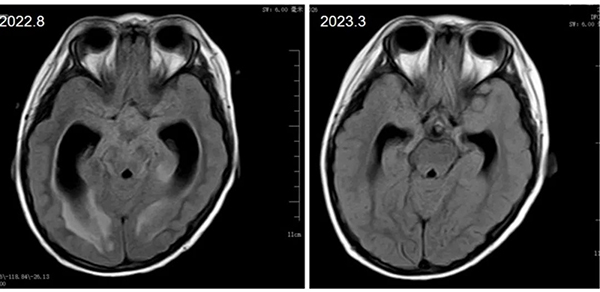

5岁的瑶瑶,因发热、嗜睡、意识模糊救治于当地医院,在症状逐渐加重,出现昏迷的情况下转诊至沈阳市第十人民医院,经学生儿童结核科陈禹主任及时会诊考虑结核性脑膜炎转入医院就诊。学生儿童结核科科主任、护士长高度重视小患者的病情,及时进行了规范的床旁体格检查及腰椎穿刺术等,第一时间为患儿确诊结核性脑膜炎。学生儿童结核科团队在考虑患者年龄小、体质弱、病情重等特点后,有针对性的分析病情疑难点,制定个性化治疗方案、严格计算药物剂量并结合相应辅助治疗手段,护理团队也对小患者进行相应护理评估,从治疗、生活、心理,给予小患者全方位精细化照护。在治疗的过程中,也帮助孩子妈妈树立了信心,从绝望中走出。虽然治疗过程艰难而复杂,但在学生儿童结核科团队全体医护人员饱满的工作热情、精心的医疗服务以及温馨的护理关怀下,瑶瑶一天天好起来,从能睁眼、能进食、能吐字、上肢能逐渐活动到能下地走路、迎面跑来、给医务人员热情的拥抱,现已成功治愈出院。